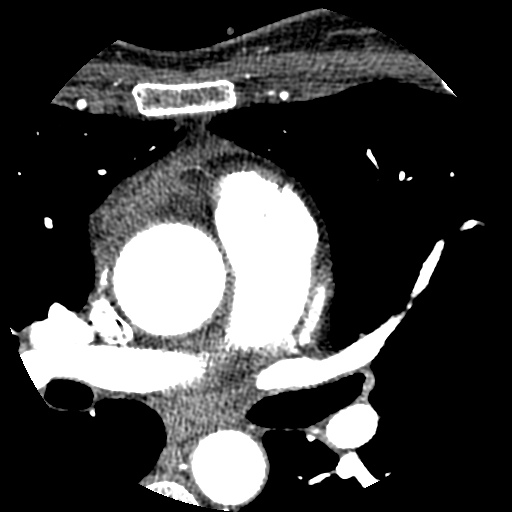

Cardio CT

Selezione di sezioni assiali ottenute con iniezione intravenosa del mezzo di contrasto